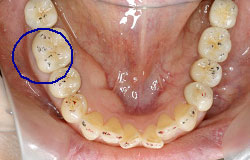

インプラントで噛み合わせの再構成を伴った症例。

治療後のメンテナンスを行わないと

周囲炎になるリスクあり。